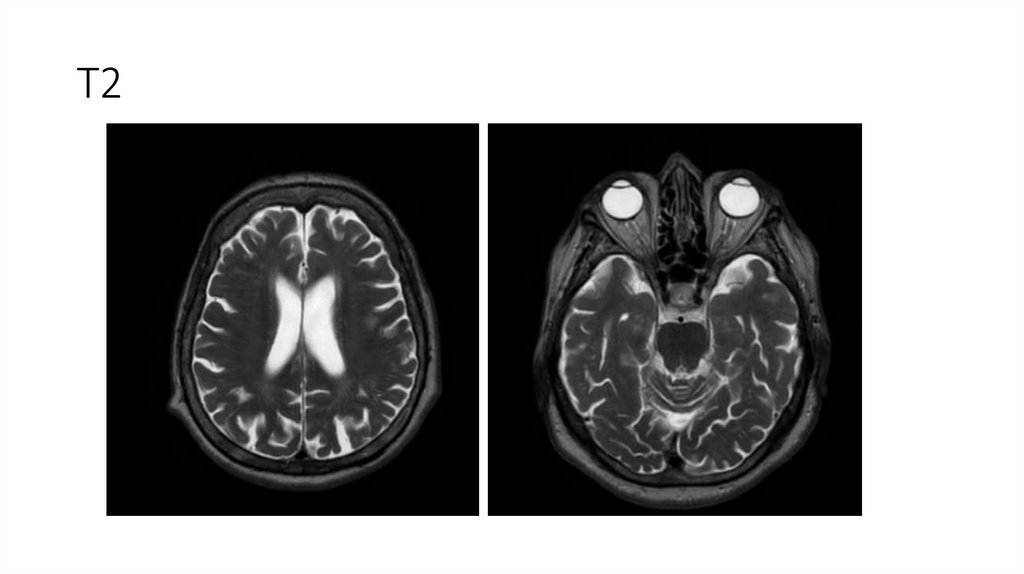

18. МРТ ГМ от 08.04.2025

Описание

-Срединные структуры не смещены.

-Желудочки обычной формы и размеров.

-Субарахноидальные пространства не расширены.

-Дифференциация серого и белого вещества сохранена.

-В белом веществе головного мозга, в паравентрикулярных и конвекситальных областях визуализируются множественные очаги

диаметрами 3-10мм, вероятно, сосудистого генеза.

-Отмечается незначительное расширение периваскулярных пространств.

-МР-сигнал от подкорковых ядер не изменен.

-Селлярная область без патологических изменений.

-Размеры гипофиза в пределах нормы.

-Стволовые структуры и мозжечок в пределах нормы.

-Мостомозжечковые углы без особенностей.

-Краниовертебральный переход не изменен.

-Придаточные пазухи и ячейки сосцевидных отростков воздушны.

-Содержимое глазниц без особенностей. ;

Заключение

• МР-картина множественных очагов в белом веществе головного мозга, вероятно,

сосудистого генеза.

20. T2